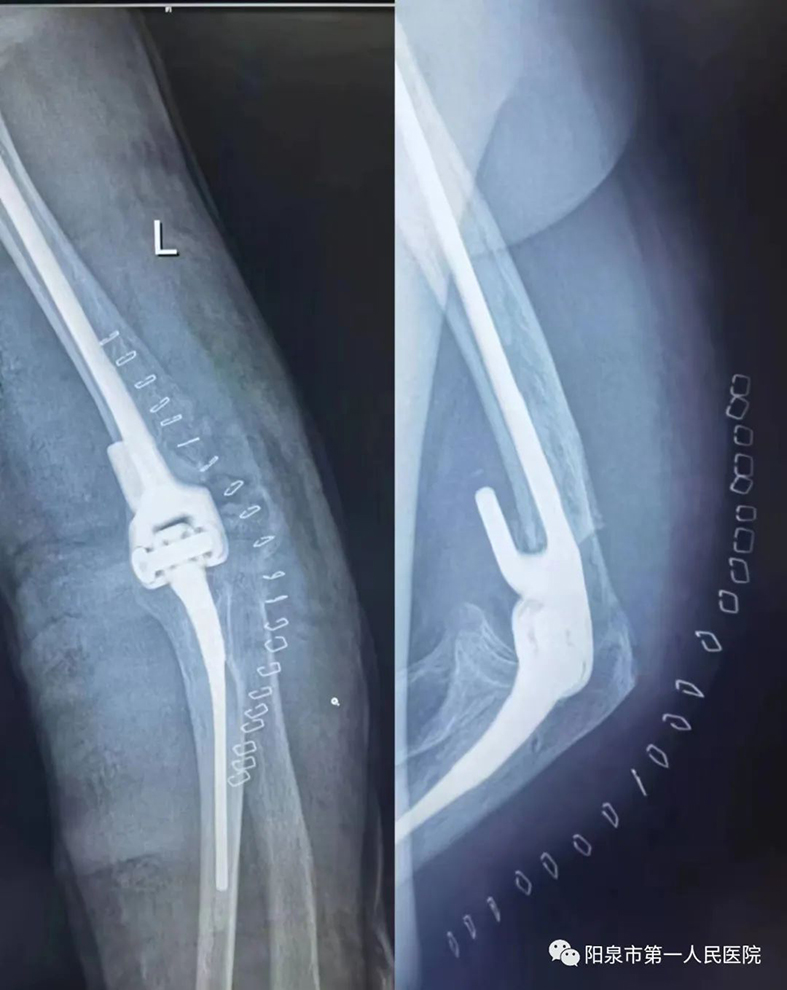

1月16日,山西省医院协会理事单位——阳泉市第一人民医院关节外科主任葛建忠博士,带领张勇威主任医师、许鹏医师和王凯医师,为一位74岁的老人施行全肘关节置换术,获得成功。这在该院尚属首例,也是该院骨科手术团队在累计完成上千例髋、膝关节置换及肩关节置换手术的基础上开展的新手术方法。

该患者因外伤致左肘关节粉碎性骨折,保守治疗和复位固定效果均不理想,全肘关节置换是解决该疾患的良好选择。在患者局部消肿一周后,葛建忠博士团队成功地为其行全肘关节置换。目前,患者已顺利出院。

全肘关节置换术是目前世界上开展相对较少的手术。它对手术医师的操作准确性要求严格,并且对软组织平衡及假体的匹配要求非常高。施行人工全肘关节置换术能为复杂的肘关节疾患提供可行的治疗方法,可达到解除疼痛,恢复肘部运动及稳定性、改善患者生活质量的目的。